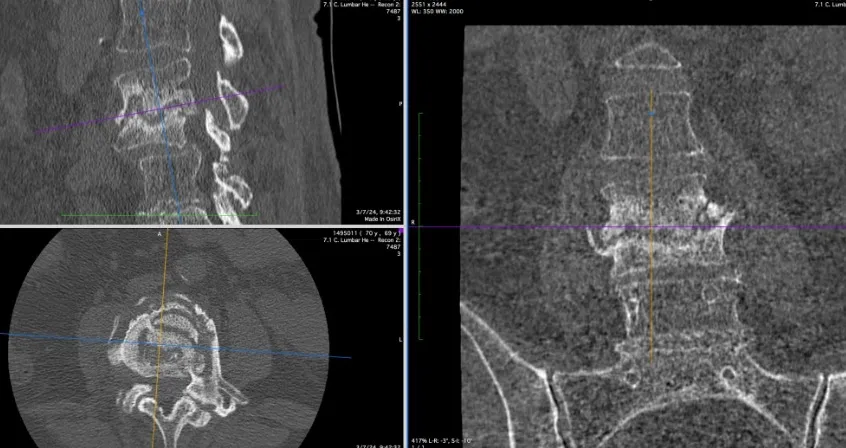

Tomografía computarizada (TAC)

El TAC es superior a la radiografía para visualizar el disco intervertebral, los cuerpos vertebrales y el grado de destrucción ósea. Es especialmente útil para guiar biopsias percutáneas y valorar los estadios de fusión vertebral. Sin embargo, su sensibilidad (67%) y especificidad (54%) son limitadas para el diagnóstico inicial.

Biopsia percutánea guiada por TAC: cuando los hemocultivos son negativos, se puede realizar una punción directa del disco o del cuerpo vertebral afectado bajo control tomográfico. Esta técnica obtiene material para cultivo y estudio anatomopatológico con un rendimiento diagnóstico del 56%.